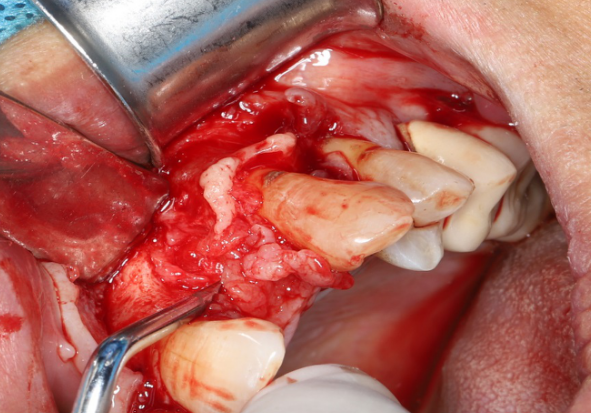

使用12#镰形刀片沿21、22、23做龈沟内切口,于24近中做垂直附加切口。

翻开全厚粘骨膜瓣,暴露22颊侧牙槽骨,微创拔除22。

搔刮22拔牙创,暴露22牙槽骨表面,开放骨髓腔。

采用不切开骨膜的软组织扩张术——Soft Tissue Extend释放软组织张力

记录翻瓣后原始软组织瓣长度,使用软组织搔刮器(Soft Tissue Extender)冠根向搔刮软组织瓣。

在不切断骨膜的前提下,使用软组织刮治器反复搔刮软组织瓣,可以起到延长软组织瓣的作用。

使用软组织搔刮扩张前后对比:可见在不切断骨膜的前提下,使用软组织搔刮即可获得软组织瓣延长8-9mm。